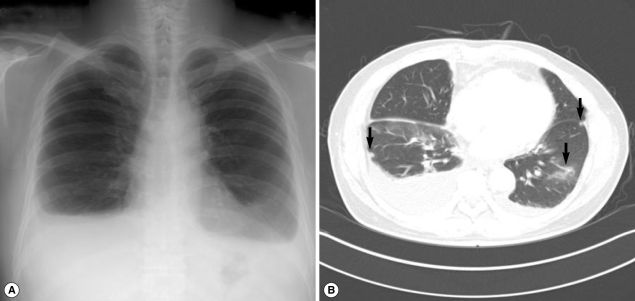

Fig. 2

Simple chest x-ray and CT findings in case 2. (A) Extensive pleural effusion is seen in both hemithoraces. (B) Atelectasis, ground-glass opacity in the lower lung and a few subpleural nodules (arrow) are observed in both lungs (arrow).

A 54-year-old man (the husband of case 1) visited our hospital to seek for treatment of sudden dyspnea accompanied by dry cough, 2 months after his wife had been treated for paragonimiasis. He had previously been healthy with no prior medical problems. However, his body weight decreased by 4 kg. He had eaten Kejang with her wife during the same period. On physical examination, his breathing sound was decreased in the lower lung zone. A CBC revealed WBC level of 21,800/mm3, hemoglobin level of 13.5 g/dl, platelet level of 258,000/mm3, and AEC of 13,580/mm3. Other laboratory tests revealed no abnormal findings. A simple chest x-ray revealed extensive pleural effusion in both hemithoraces (Fig. 2A). A chest CT also revealed extensive pleural effusion, as well as atelectasis and ground glass opacity in the lower lung and pleural nodules (Fig. 2B). According to the laboratory findings, image work-up, and recorded family history, stool examinations and ELISA tests were followed. As a result, Paragonimus eggs were observed in the stool sample, and ELISA test was positive for antibodies against Paragonimus westermani. The patient's total serum IgE level was 341 kU/L (cut-off level; below 100 kU/ml). On the basis of these findings, the patient was subsequently treated with praziquantel (25 mg/kg, 3 times daily for 2 days). The patient's symptoms of dyspnea were resolved after the treatment. A week after the medication, the patient's AEC decreased from 13,580/mm3 to 7,300/mm3, and an improvement in the left pleural effusion was observed.

Fig. 2 Simple chest x-ray and CT findings in case 2. (A) Extensive pleural effusion is seen in both hemithoraces. (B) Atelectasis, ground-glass opacity in the lower lung and a few subpleural nodules (arrow) are observed in both lungs (arrow).